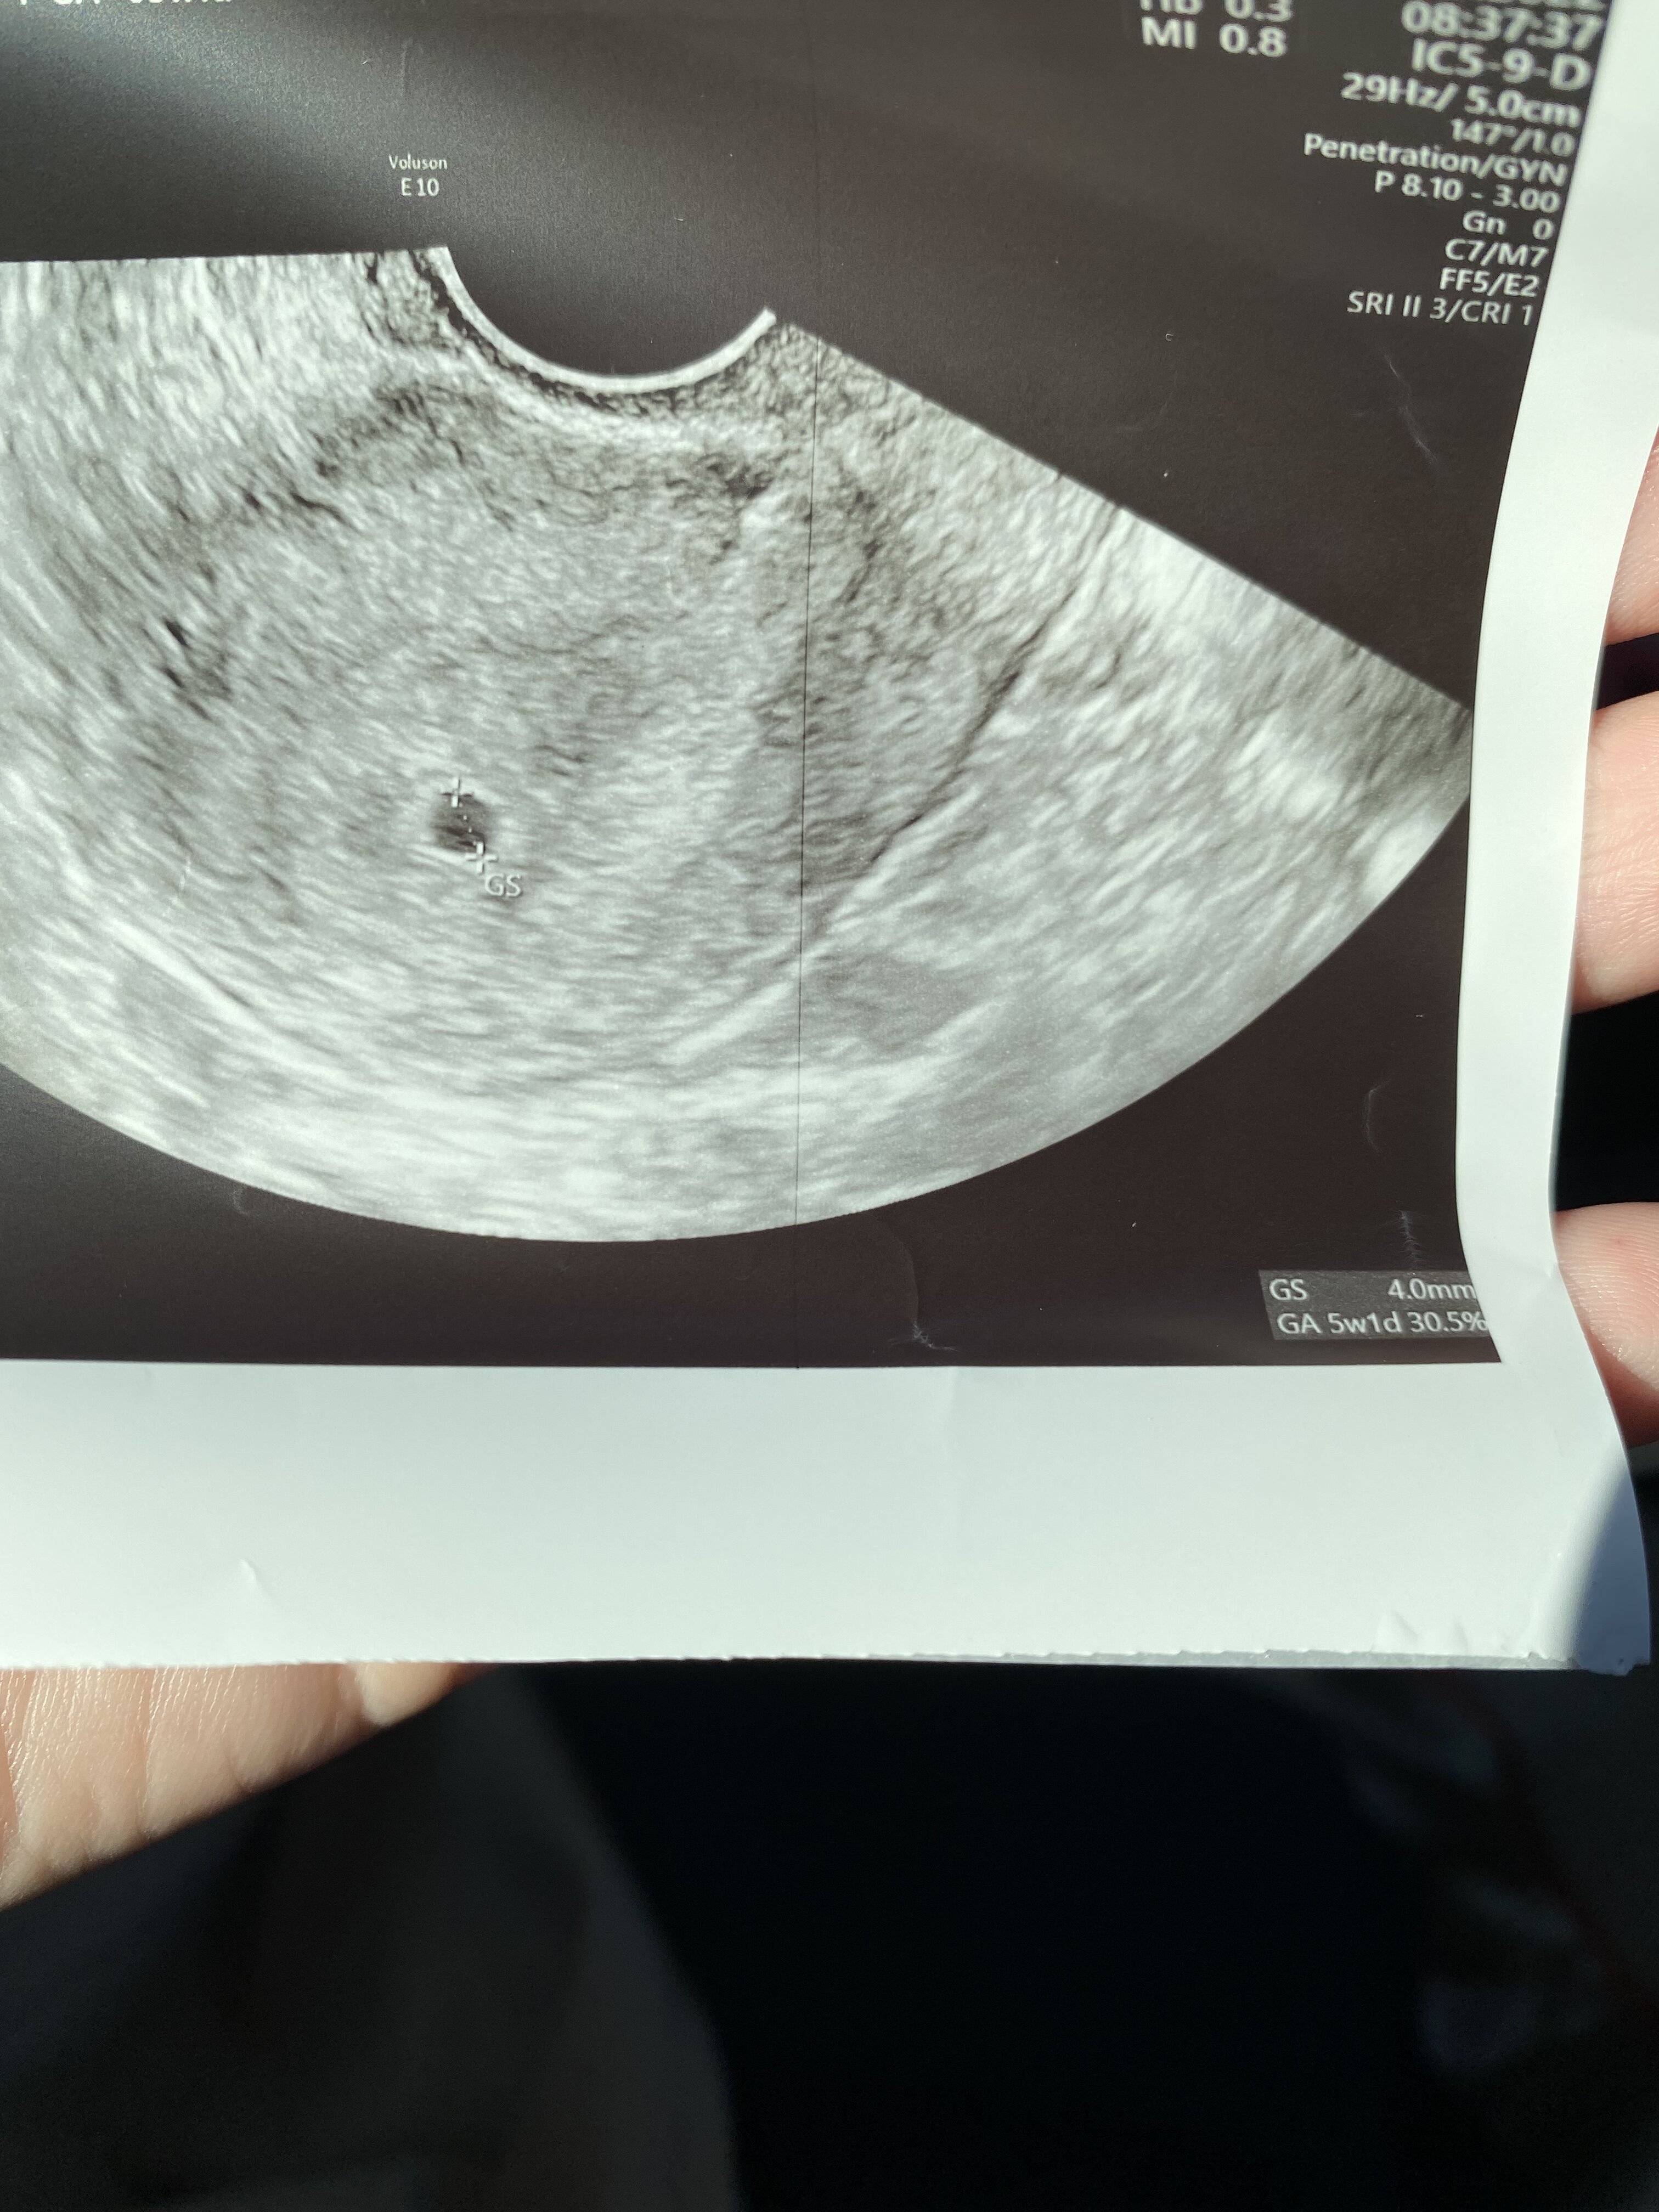

Dziewczyny. Ja byłam na wizycie rano, ale mam taki zapieprz dziś w pracy, ze dopiero mam chwile zeby skrobnąć. U mnie dziś 5+1 z terminu OM, a to usg.

Następna wizyta za 2 tyg